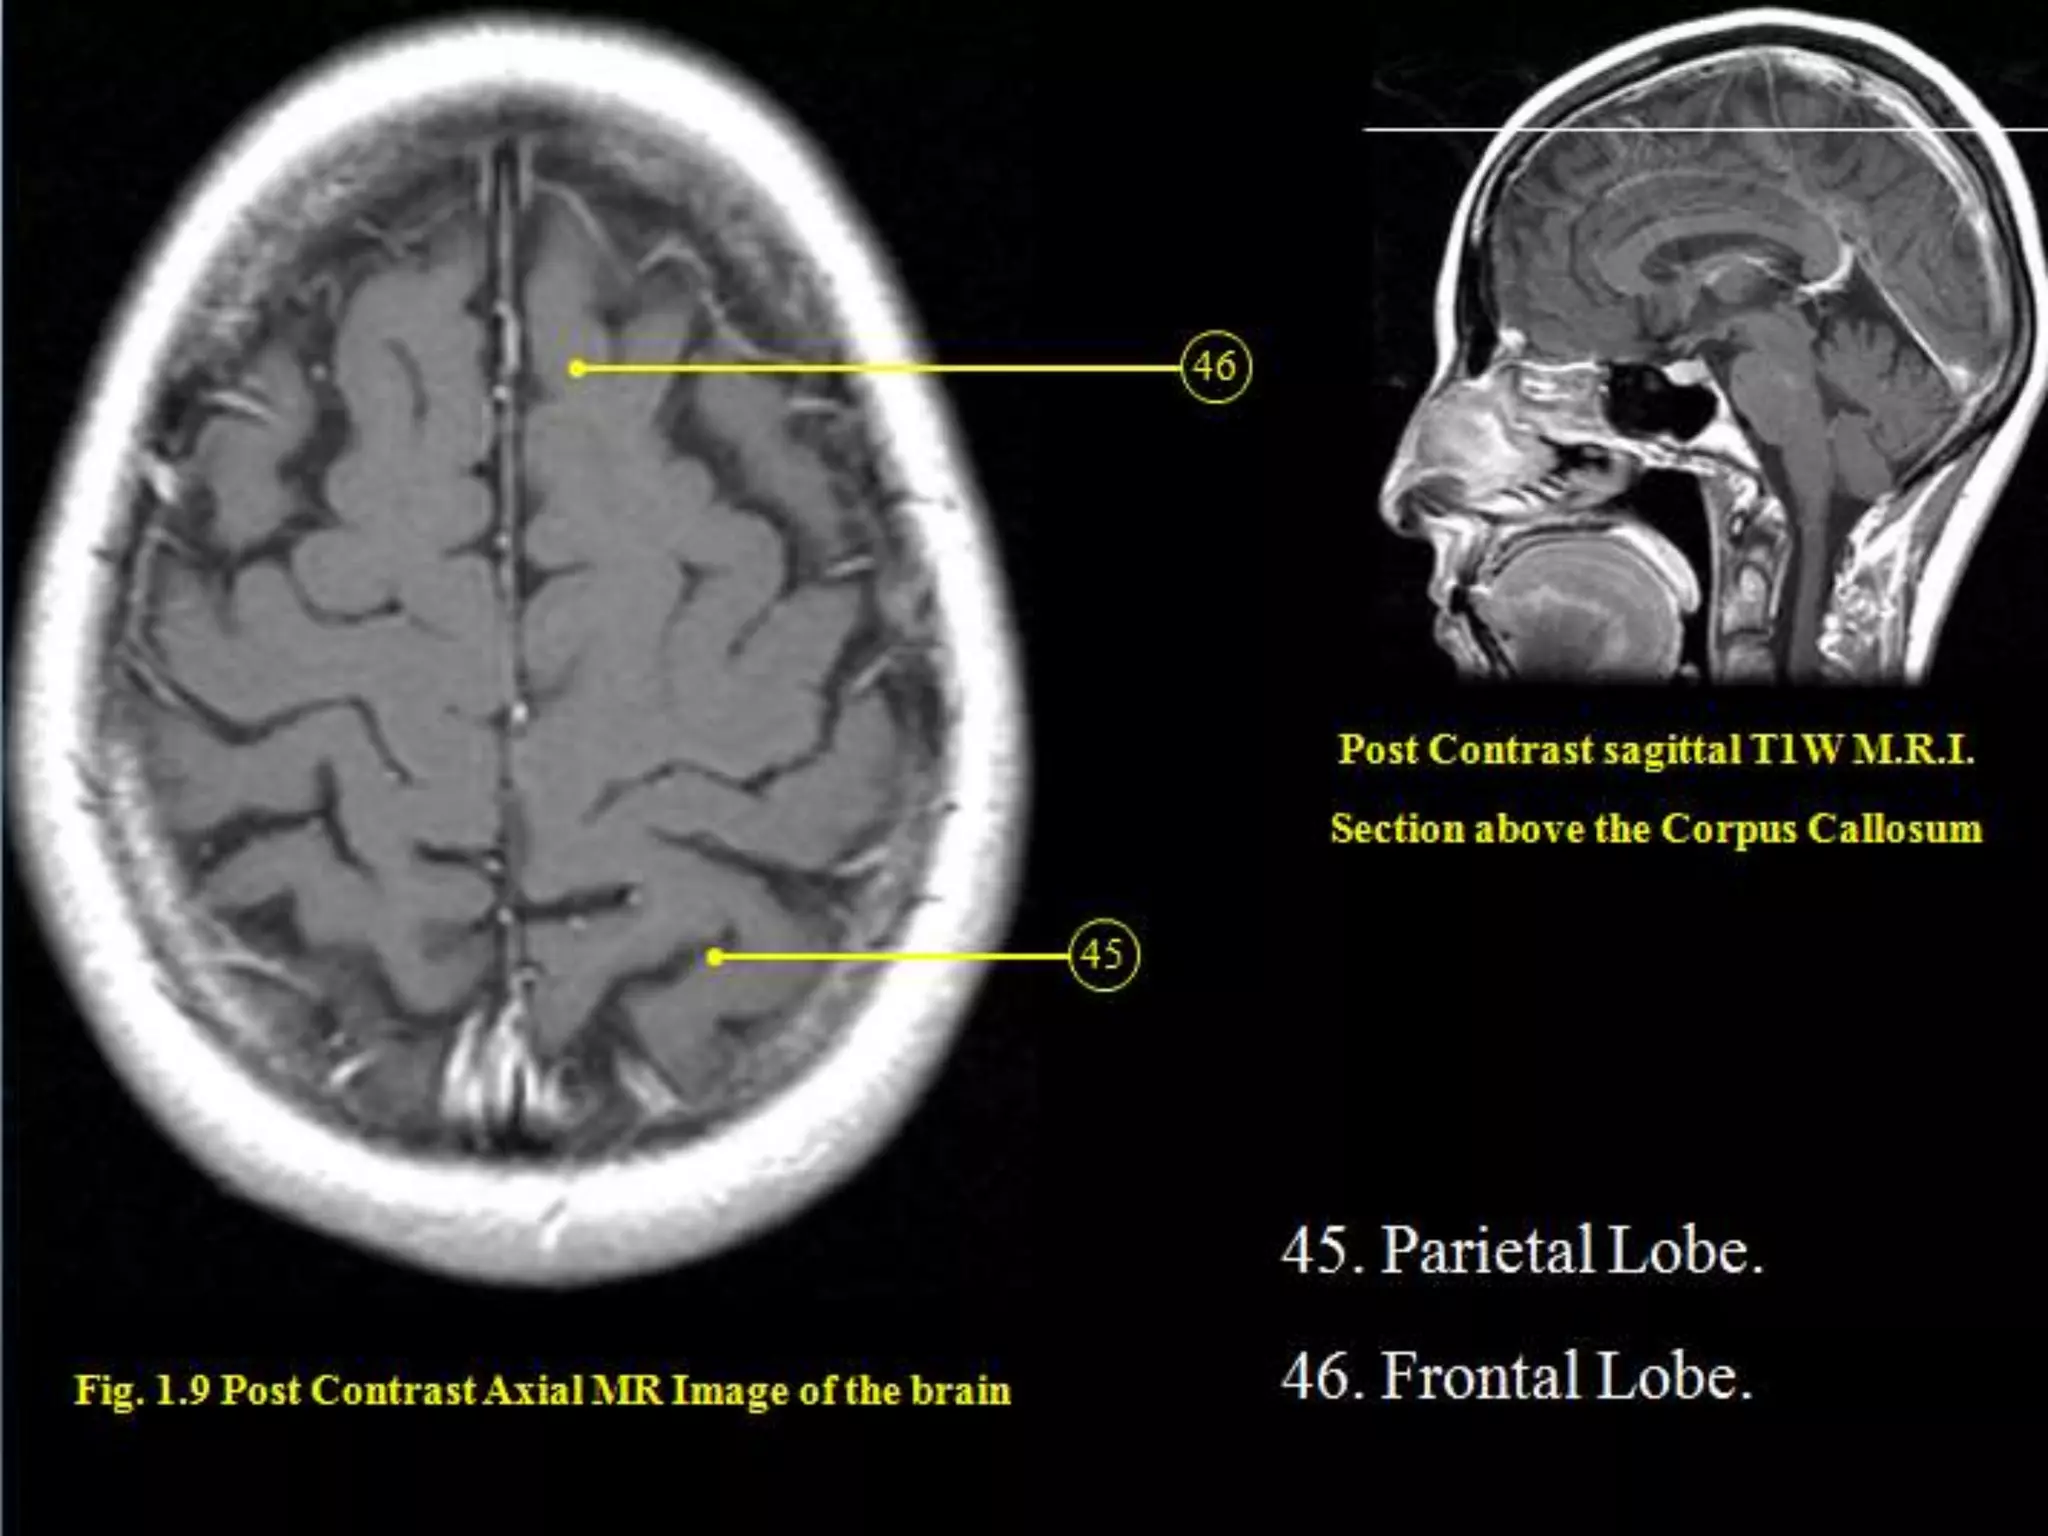

Sectional Anatomy: NormalAxial CT and MRI Anatomy. On CT and MR scans, the brain has been briefly viewed in infratentorial and supratentorial sections, as described below. CT scans are performed with a 15- to 20-degree angulation to the canthomeatal line at 8-mm increments. MRI scans are generally obtained parallel to the AC-PC line in the axial plane with 6-mm slice thickness. Using the sagittal view, the coronal sections are acquired parallel to the brain stem, and the sagittal sections are obtained perpendicular to the axial section. On MRI studies, cranial nerves IX and X can be demonstrated at this level because they emerge from the postolivary sulcus. The posterior aspect of the cerebellar hemispheres is outlined by the inferior portion of the cisterna magna.